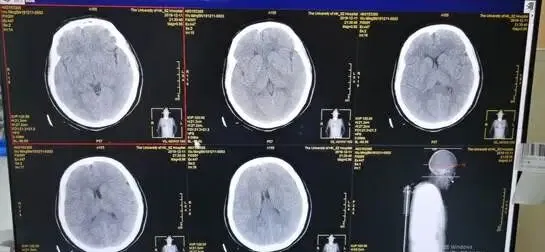

CT:脑挫伤;双侧多发肋骨骨折,左侧锁骨、肩胛骨、上胸椎多个棘突骨折,右主支气管离断,伴右侧血气胸,左主支气管损伤、腔内气管插管留置,左肺通气尚可、多发渗出;纵膈气肿,双侧颈部、胸壁皮下气肿,双侧胸腔引流术后;腹部未见异常。

CT提示右侧主支气管断裂,肺挫伤,多发肋骨骨折,左锁骨骨折,血气胸。遂急诊送手术室行胸腔探查、支气管断裂修补、左锁骨切开复位内固定手术。术后转重症监护室监护治疗,第三天评估患者病情稳定,脱机拔管,患者神志恢复,GCS15分,2周后痊愈出院,患者没有缺氧性脑病并发症。

影像科技师准备好拍片,完成床旁胸片、骨盆正位片,创伤团队即刻阅片,发现肺挫伤、右侧气胸,骨盆未见骨折。迅速于右侧第五肋间腋中线前放置胸腔闭式引流,有较多气体及少量血液引出。复测SPO2:75%,血压及心率无明显变化,末梢血循环正常,无紫绀。复查床旁胸片提示右肺没有完全复张、仍有气胸,压缩约30%,检查右侧胸腔闭式引流通畅、大量气体溢出,超声排除腹腔大出血、心包填塞可能,气管插管确定在气管内,呼吸机工作状态良好,无张力性及开放性气胸,使用储氧球囊接气管插管人工通气,发现气道阻力非常低,结合右侧胸腔闭式引流管有大量气体溢出,考虑右侧支气管损伤可能,患者SPO2继续下降至50%。立即予床旁纤维支气管镜检查,发现右侧主支气管挫伤及裂口,遂在支气管镜引导下行左侧主支气管插管并单侧肺通气,患者SPO2迅速升至98—100%,P112次/分,BP120/69mmHg。